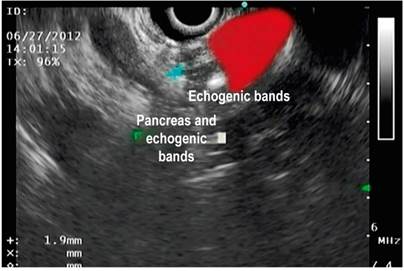

Fibrous bands (Figure 3)

Figure 3 Echogenic bands in Olympus linear endosonography (image courtesy of the Union of Surgeons SAS, Lázaro Arango).